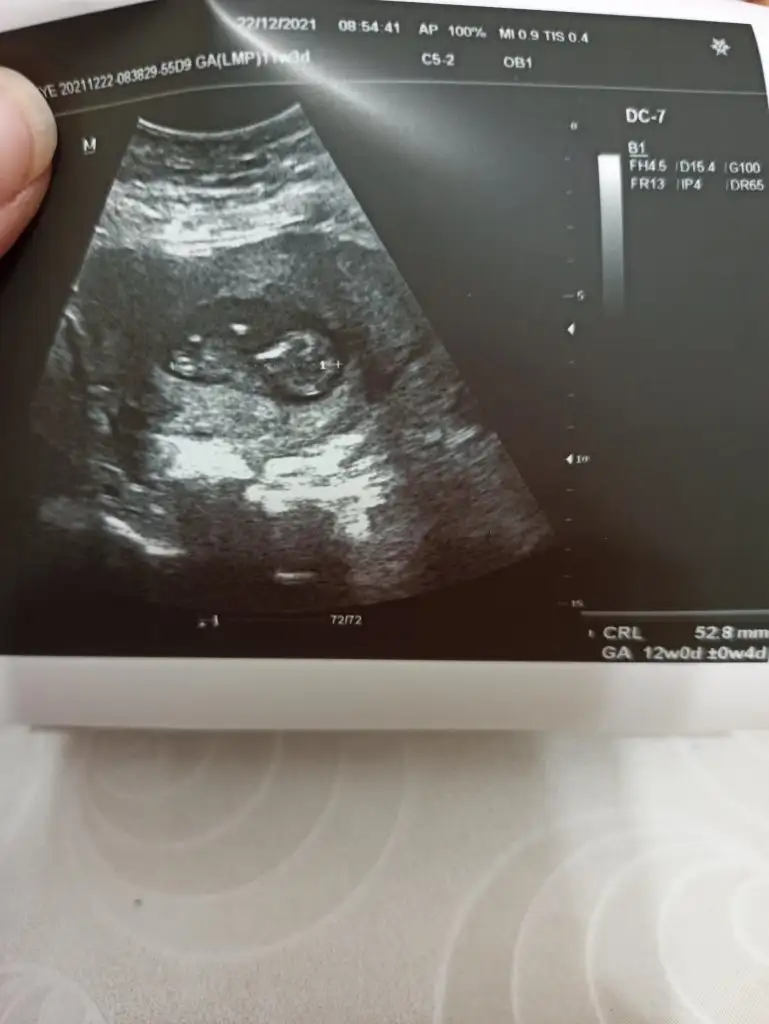

10+6 nub teorisine gore cinsiyeti nedir 🤗

• IMG_20211222_120246.webp

IMG_20211222_120246.webp

32 KB · Görüntüleme: 69